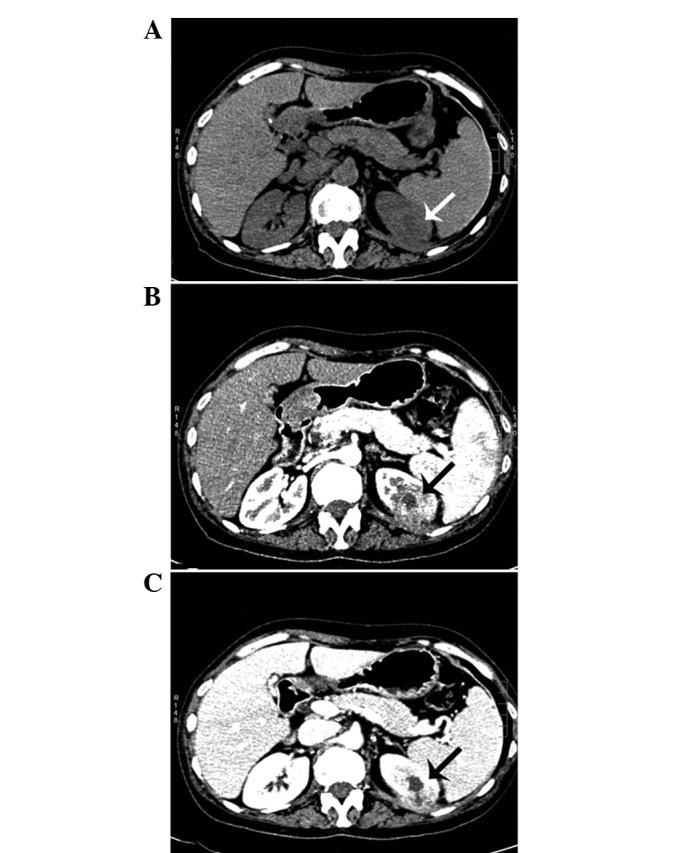

Inflammatory myofibroblastic tumor (IMT) is a rare entity that most commonly involves the lung. However, an IMT of the kidney is extremely rare. The etiology and pathogenesis of IMT remain unknown. The present study describes the case of a 48-year-old female who presented asymptomatically. Imaging investigations revealed a mass in the left kidney and a pathological examination of the nephrectomy specimen revealed an IMT. The patient had a history of trauma in the left hypochondrium 13 years previously and a history of hepatitis B for 20 years. The latter developed into hepatic cirrhosis, hypersplenism and coagulation disorders, which may play have played a significant role in the development of the IMT of the kidney in the present case and also may aid in improving the understanding of the etiology and pathogenesis of IMT of the kidney.